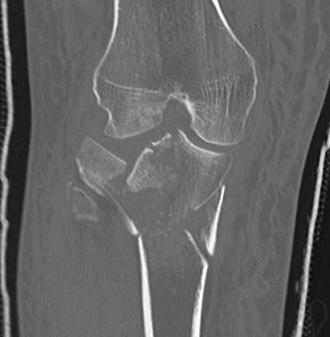

CT scan

Assess joint line

- predetermine fracture pattern before fixation

- will pick up medial condyle / bicondyle / metaphyseal fractures not seen on xray